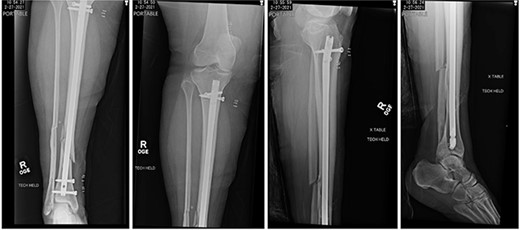

A 34-year-old obese female (body mass index of 48.17 mg/kg2) presented to a level 1 trauma center after experiencing a ground level fall and sustaining a displaced Gustilo-Anderson grade 1 open comminuted spiral fracture of the right distal tibial shaft (OTA classification 42A1c) (Fig. 1). Other injuries included a displaced comminuted distal fibula fracture and a nondisplaced proximal fibular neck fracture. In the emergency department, the 1.5 cm wound over the distal anteromedial tibia was irrigated with 3 L of normal saline, and the fracture was reduced and splinted.

Initial radiographs demonstrating fractures of the proximal fibular neck and distal tibia and fibula.